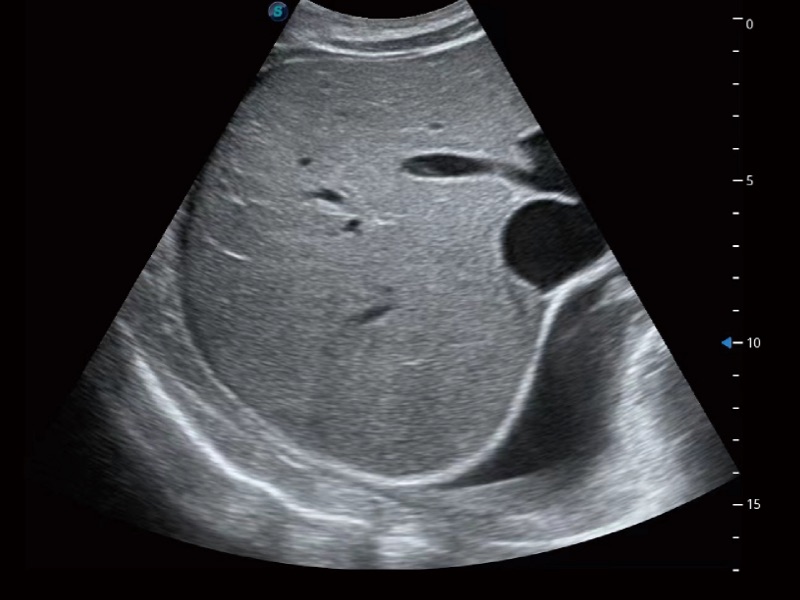

腹部应用

宽频带及多频段变频结合诸侯快讯官网频率复合技术,使得每一支探头可以很好地给临床带来穿透力与分辨率的完美结合,图像真实,提供临床诊断准确性。

微米成像技术大大提高了器官和病变的可见性。高清对比度分辨率将抑制斑点噪声,同时保持真实的组织结构。